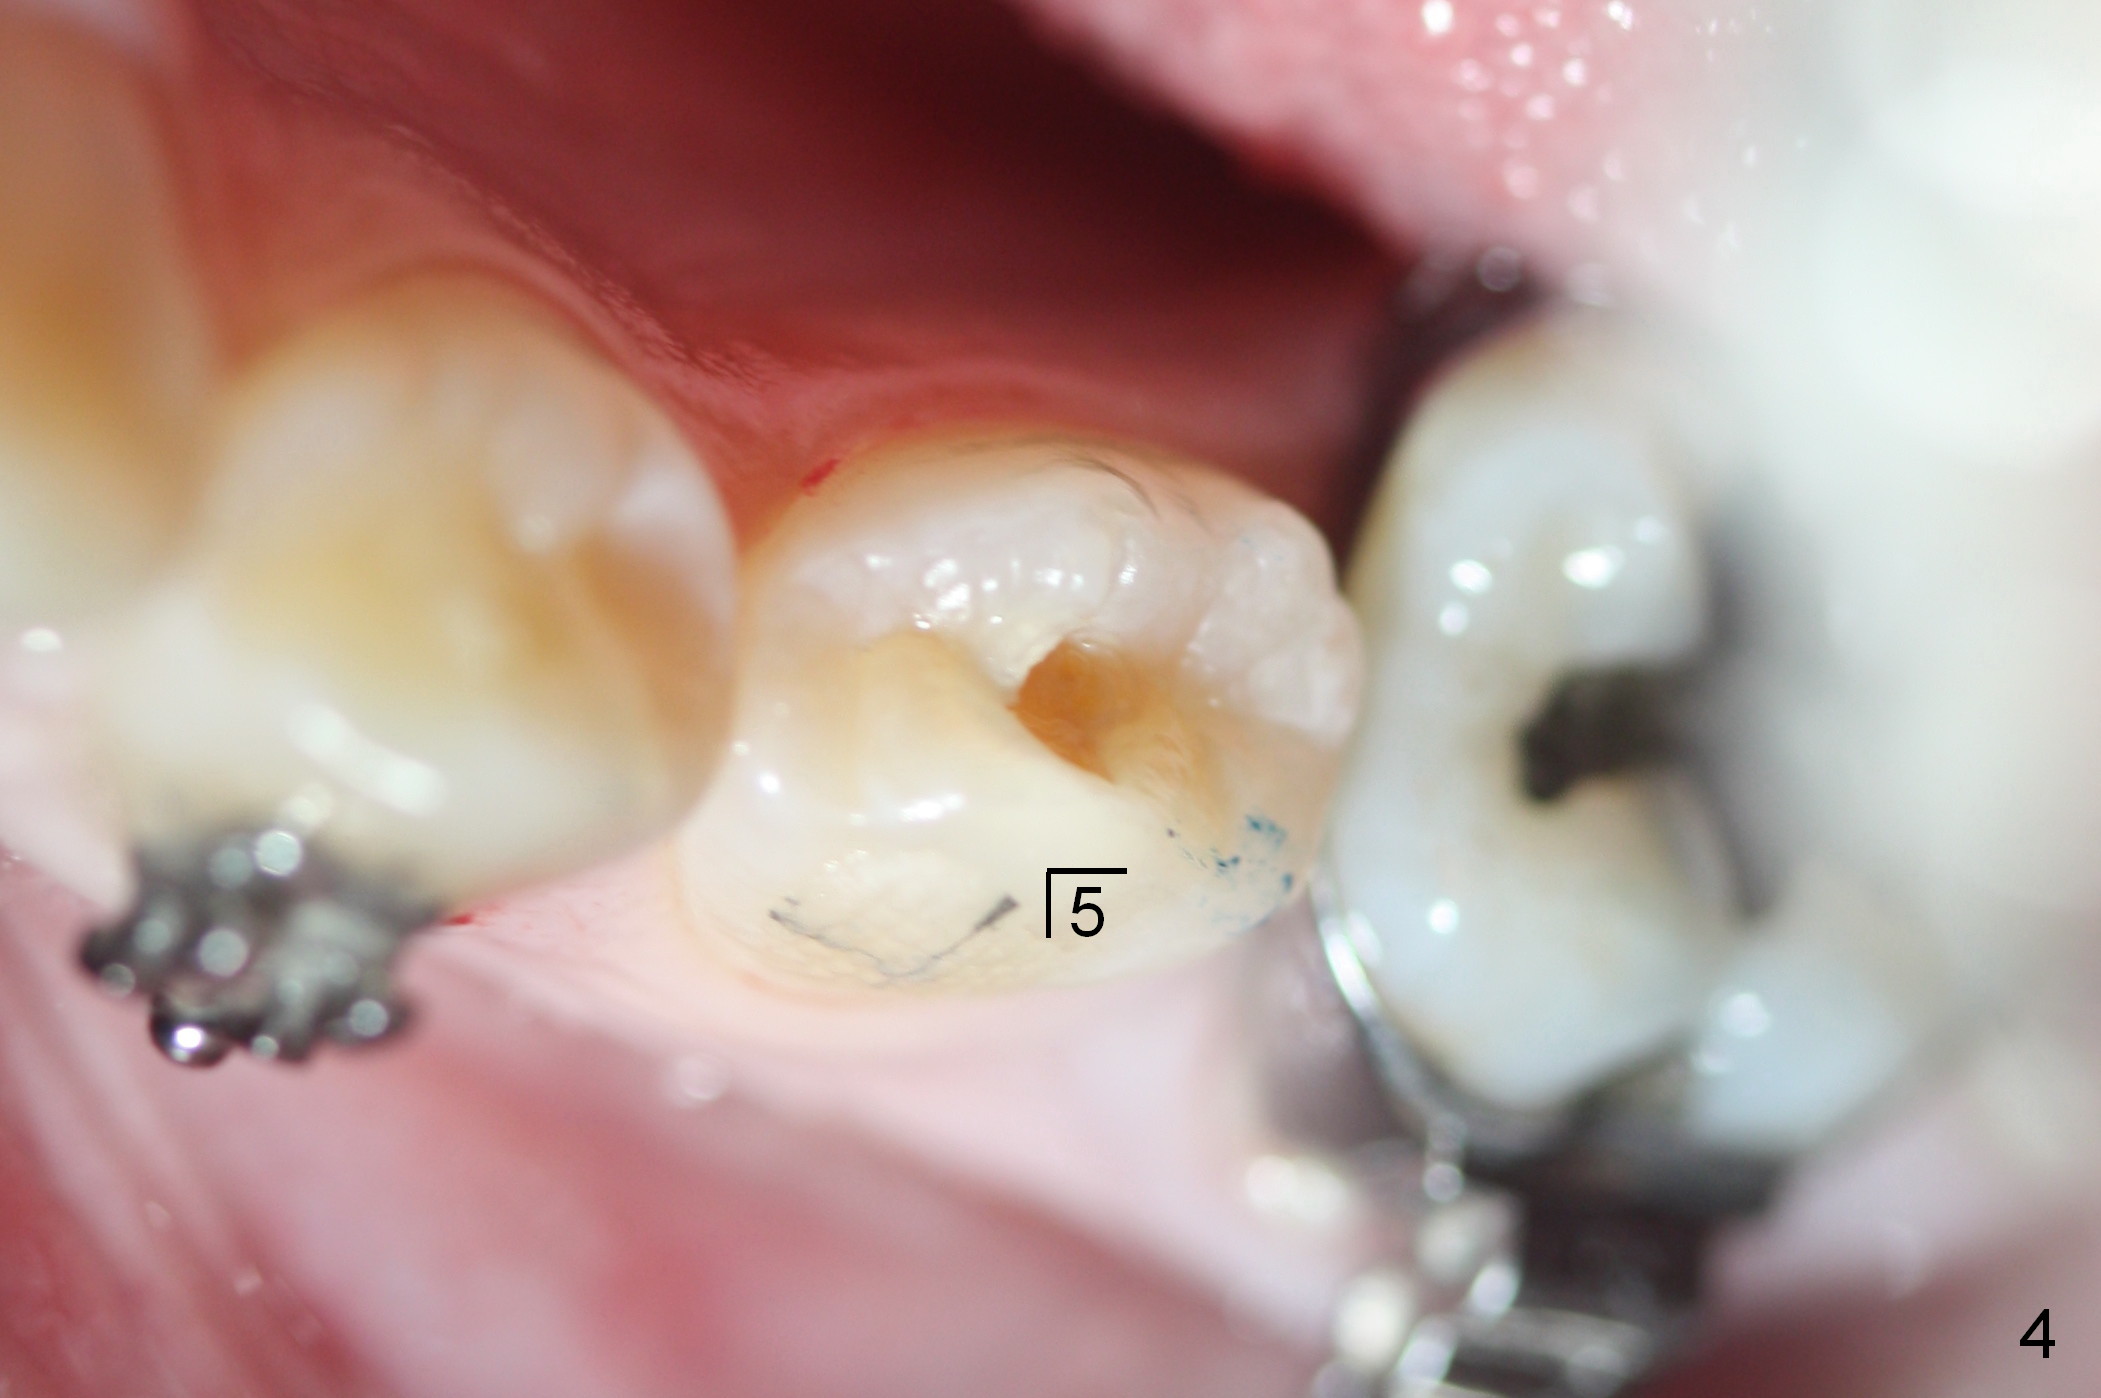

A 15-year-old Spanish female has been in orthodontic treatment for 2 years 3 months (1 2 3). Facial profile is convex (same as preop (Fig.5-8)) with anterior open bite (Fig.1,2). Four bicuspid extraction is considered. Since brackets of the 2nd bicuspids have been lost (Fig.1,2) and there are pathologies associated with the lower ones (Fig.3,4), all of the 2nd bicuspids have been extracted. Plan is to retract the 1st bicuspids, canines and incisors sequentially. How to close the anterior open bite?

Approximately 4.5 months of power chains between 4s and 6s buccally, U4s contact U6s with rotation (Fig.13,14), while L4s have 1-2 mm to be distalized (Fig.15,16). With placement of lingual buttons on U4s and power chains lingually, the rotation should be corrected. The rotation wedges were placed with ligature wire on the left in the last visit. The patient returns 3 weeks later.